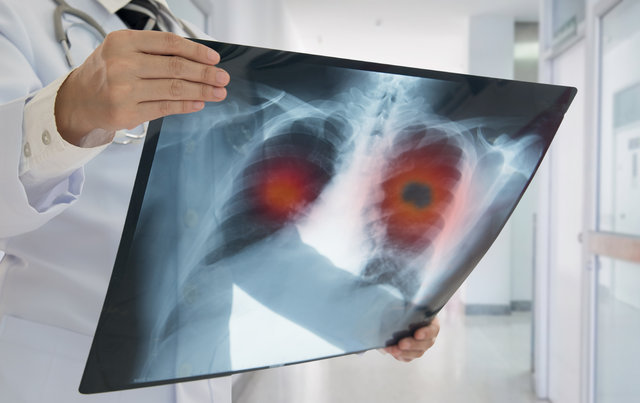

Tıbbi Onkoloji Uzmanı Prof. Dr. Emin Gökhan Kandemir, en ölümcül kanserlerden biri olan akciğer kanserinin belirtileri ve tedavisi hakkında bilinmesi gerekenleri anlattı.

Günümüzde kanser vakalarına bakıldığında kalın bağırsak, meme ve prostat kanseri nedeniyle yaşamını yitirenlerin toplamından daha fazla kişi akciğer kanseri nedeniyle hayatını kaybediyor.